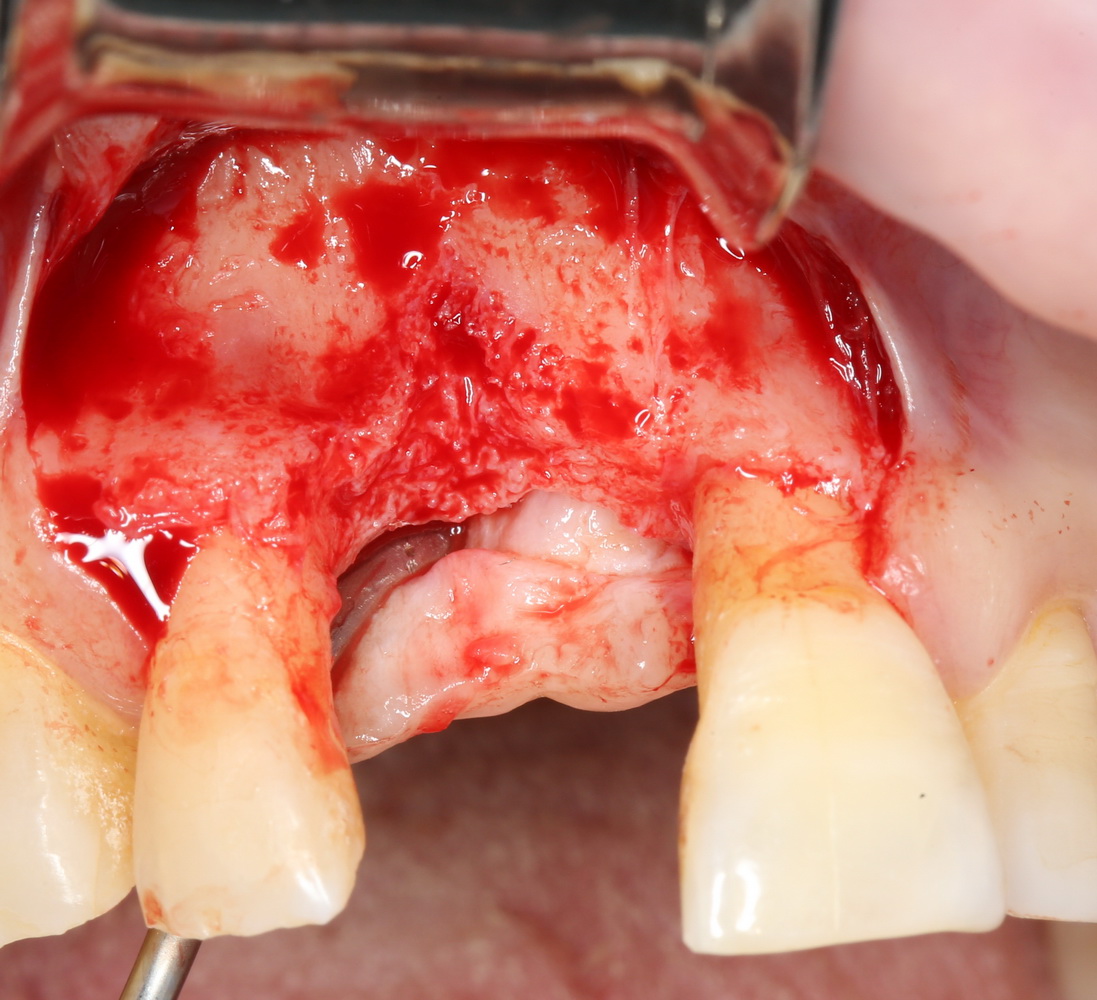

Другой вариант. Имплантируем, но существующего объема костной ткани недостаточно для получения адекватного эстетического и функционального результата:

Поэтому мы используем мембрану Geistlich BioGide и всё ту же аутокостную стружку: